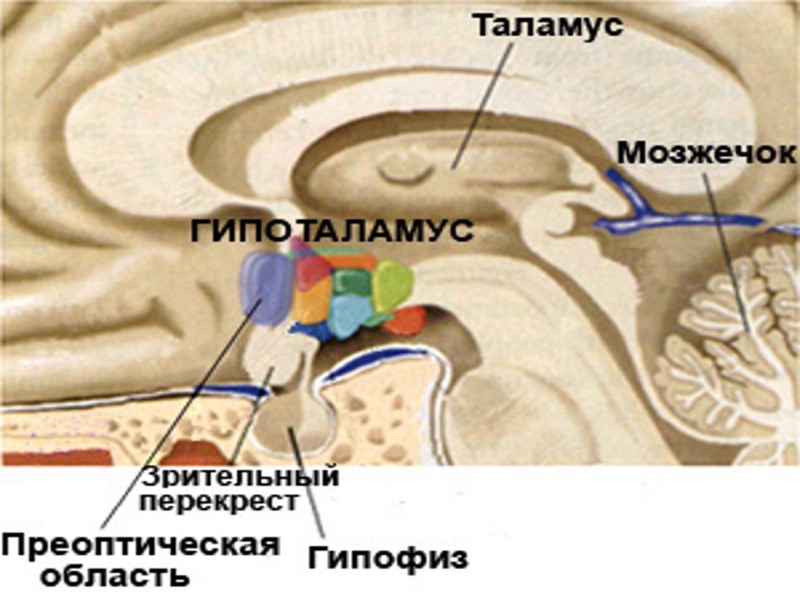

Гипоталамо-гипофизарно нейросекреторный комплекс – высший нейроэндокринный трансмиттер организма, координирующий эндокринную регуляцию метаболизма с работой ВНС и интегральными эмоционально-поведенческими реакциями лимбической системы. Состоит из: - Гипоталамус; - Нейрогипофиз; - Аденогипофиз

Гипоталамус – отдел промежуточного мозга, обеспечивающий контроль установочных точек гемостаза: - термостатная установочная точка; - массостатная установочная точка; - осмостатная установочная точка; - баростатический центр и др…

Гипофиз – орган, обеспечивающий процессы метаболизма и репродукции организма. - Аденогипофиз; - Нейрогипофиз